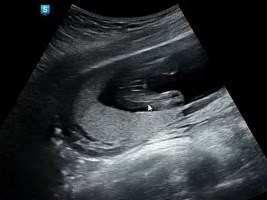

오늘 드디어 행복이의 성별을 알게된다.

우리 행복이는 아들이었다.